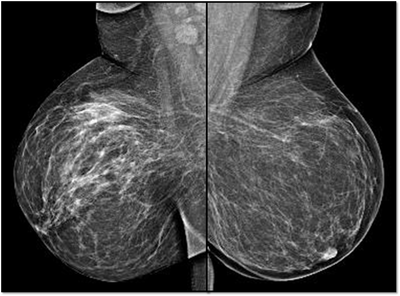

MG: Right breast shows focal asymmetric density in lateral quadrant extending for an area of 12.4 x 6.5 cm with no associated discrete mass or suspicious calcifications. Correlative ultrasound showed a heterogeneous area with echogenic vascular surrounding parenchyma in lateral quadrant with no discrete solid masses. MRI breast was performed on day 14 of LMP. Right breast shows an area predominantly consisting of fat in lateral quadrant extending for an area of 1.2×5.5x 8.9 cm along its maximum AP, ML and CC dimensions. This area is bright on fat suppressed T2 sequences and shows significant restriction on diffusion weighted sequences. There is rapid and progressive non mass enhancement in the above area extending anteriorly in to the nipple and posteriorly into the pectoralis major muscle. Two large and tortuous feeding vessels are seen to arise from the subclavian and axillary arteries respectively. Right breast shows predominantly fat containing mass showing abnormal enhancement described. The possibilities include vascular neoplasm or remotely fat necrosis. Ultrasound guided core biopsy was Suggestive of an inflammatory lesion, possibly fat necrosis. However enlarged and tortuous feeding arteries to the vascular mass was worrisome and we recommended an excision biopsy correlation. Excision biopsy showed “Multiple patchy areas of dense inflammatory infiltration in a background of fat necrosis”.